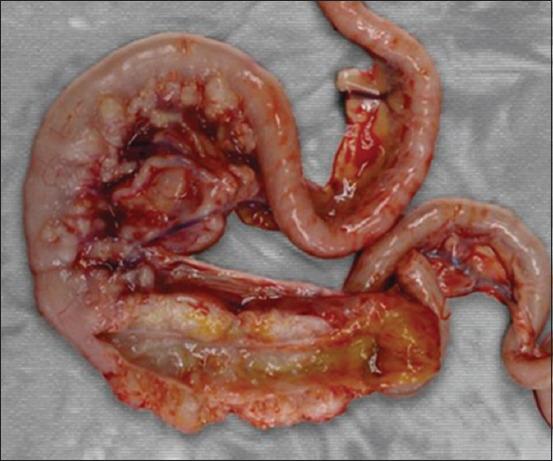

Feline infectious peritonitis (FIP) is an infectious disease characterized by non-specific laboratory changes and clinical signs. Clinical symptoms include anorexia, jaundice, fever, and weight loss. Moreover, some lesions are found in the digestive and respiratory systems. FIP, whose virulence varies, cannot be distinguished using several diagnostic methods. Moreover, feline coronaviruses (FCoVs) can be classified into two serotypes based on differences in their amino acid sequences, spike (S) protein sequences, and antibody (Ab) neutralization. There are two pathotypes, namely those caused by FCoV, which are often referred to as feline enteric coronavirus and FIP virus (FIPV). Furthermore, FIPV infection can be caused by sub-neutralizing levels of anti-FIPV S Abs. Therefore, a supporting diagnosis is needed to confirm FIP because there are no specific symptoms. This review aimed to provide updated information on FIP, including epizootiology, clinical and pathological characteristics, pathogenesis, hematology, clinicopathological and imaging features, pathological features, experimental infection, treatment and prevention, infection and immunity, animal and public health considerations.

猫传染性腹膜炎(FIP)是一种以非特异性实验室变化和临床症状为特征的传染病。临床症状包括厌食、黄疸、发热和体重减轻。此外,在消化系统和呼吸系统中发现了一些病变。FIP的毒力各不相同,无法通过几种诊断方法进行区分。此外,猫冠状病毒(FCoV)可根据其氨基酸序列、刺突(S)蛋白序列和抗体(Ab)中和作用的差异分为两种血清型。有两种致病型,即由FCoV引起的,通常称为猫肠道冠状病毒和FIP病毒(FIPV)。此外,FIPV感染可能由抗FIPV S抗体的亚中和水平引起。因此,由于没有特异性症状,需要进行辅助诊断来确诊FIP。本综述旨在提供有关FIP的最新信息,包括流行病学、临床和病理特征、发病机制、血液学、临床病理和影像学特征、病理特征、实验感染、治疗和预防、感染和免疫、动物和公共卫生考虑因素。